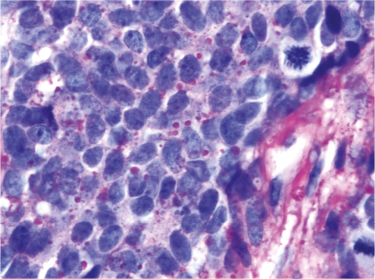

Fig 2

Figure 2. Glycogen deposits in ES/PNET. The microphotograph shows a high power view of the Ewing sarcoma/Primitive neuroectodermal tumor (ES/PNET) depicted in figure 1 with particulate of glycogen in the cytoplasm of the tumor cells and a high nucleus to cytoplasm ratio. Two mitoses (right upper corner and right lower corner) are also seen (Periodic acid Schiff staining x 630 original magnification).